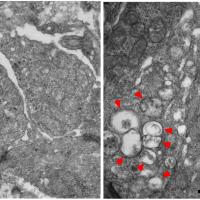

NEI researchers discover cellular events that precede neurodegenerative eye disease

Molecular and cellular changes in rod photoreceptors are detectable in a mouse model of retinal degeneration several days prior to observable morphological changes, according to researchers at the National Eye Institute.